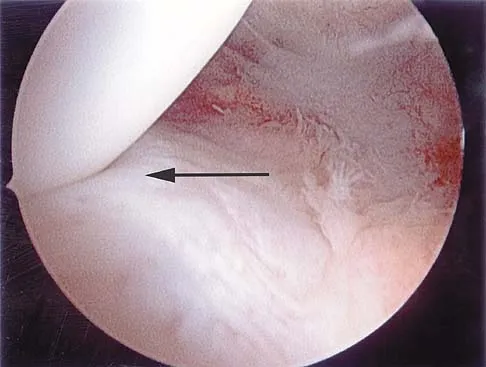

Question 60

A 29-year-old woman who underwent an anterior cruciate ligament (ACL) reconstruction 6 months ago now reports difficulty achieving full knee extension, and physical therapy fails to provide relief. The knee is stable on ligament testing. Figure 3 shows the findings at a repeat arthroscopy. Treatment should now include

Explanation